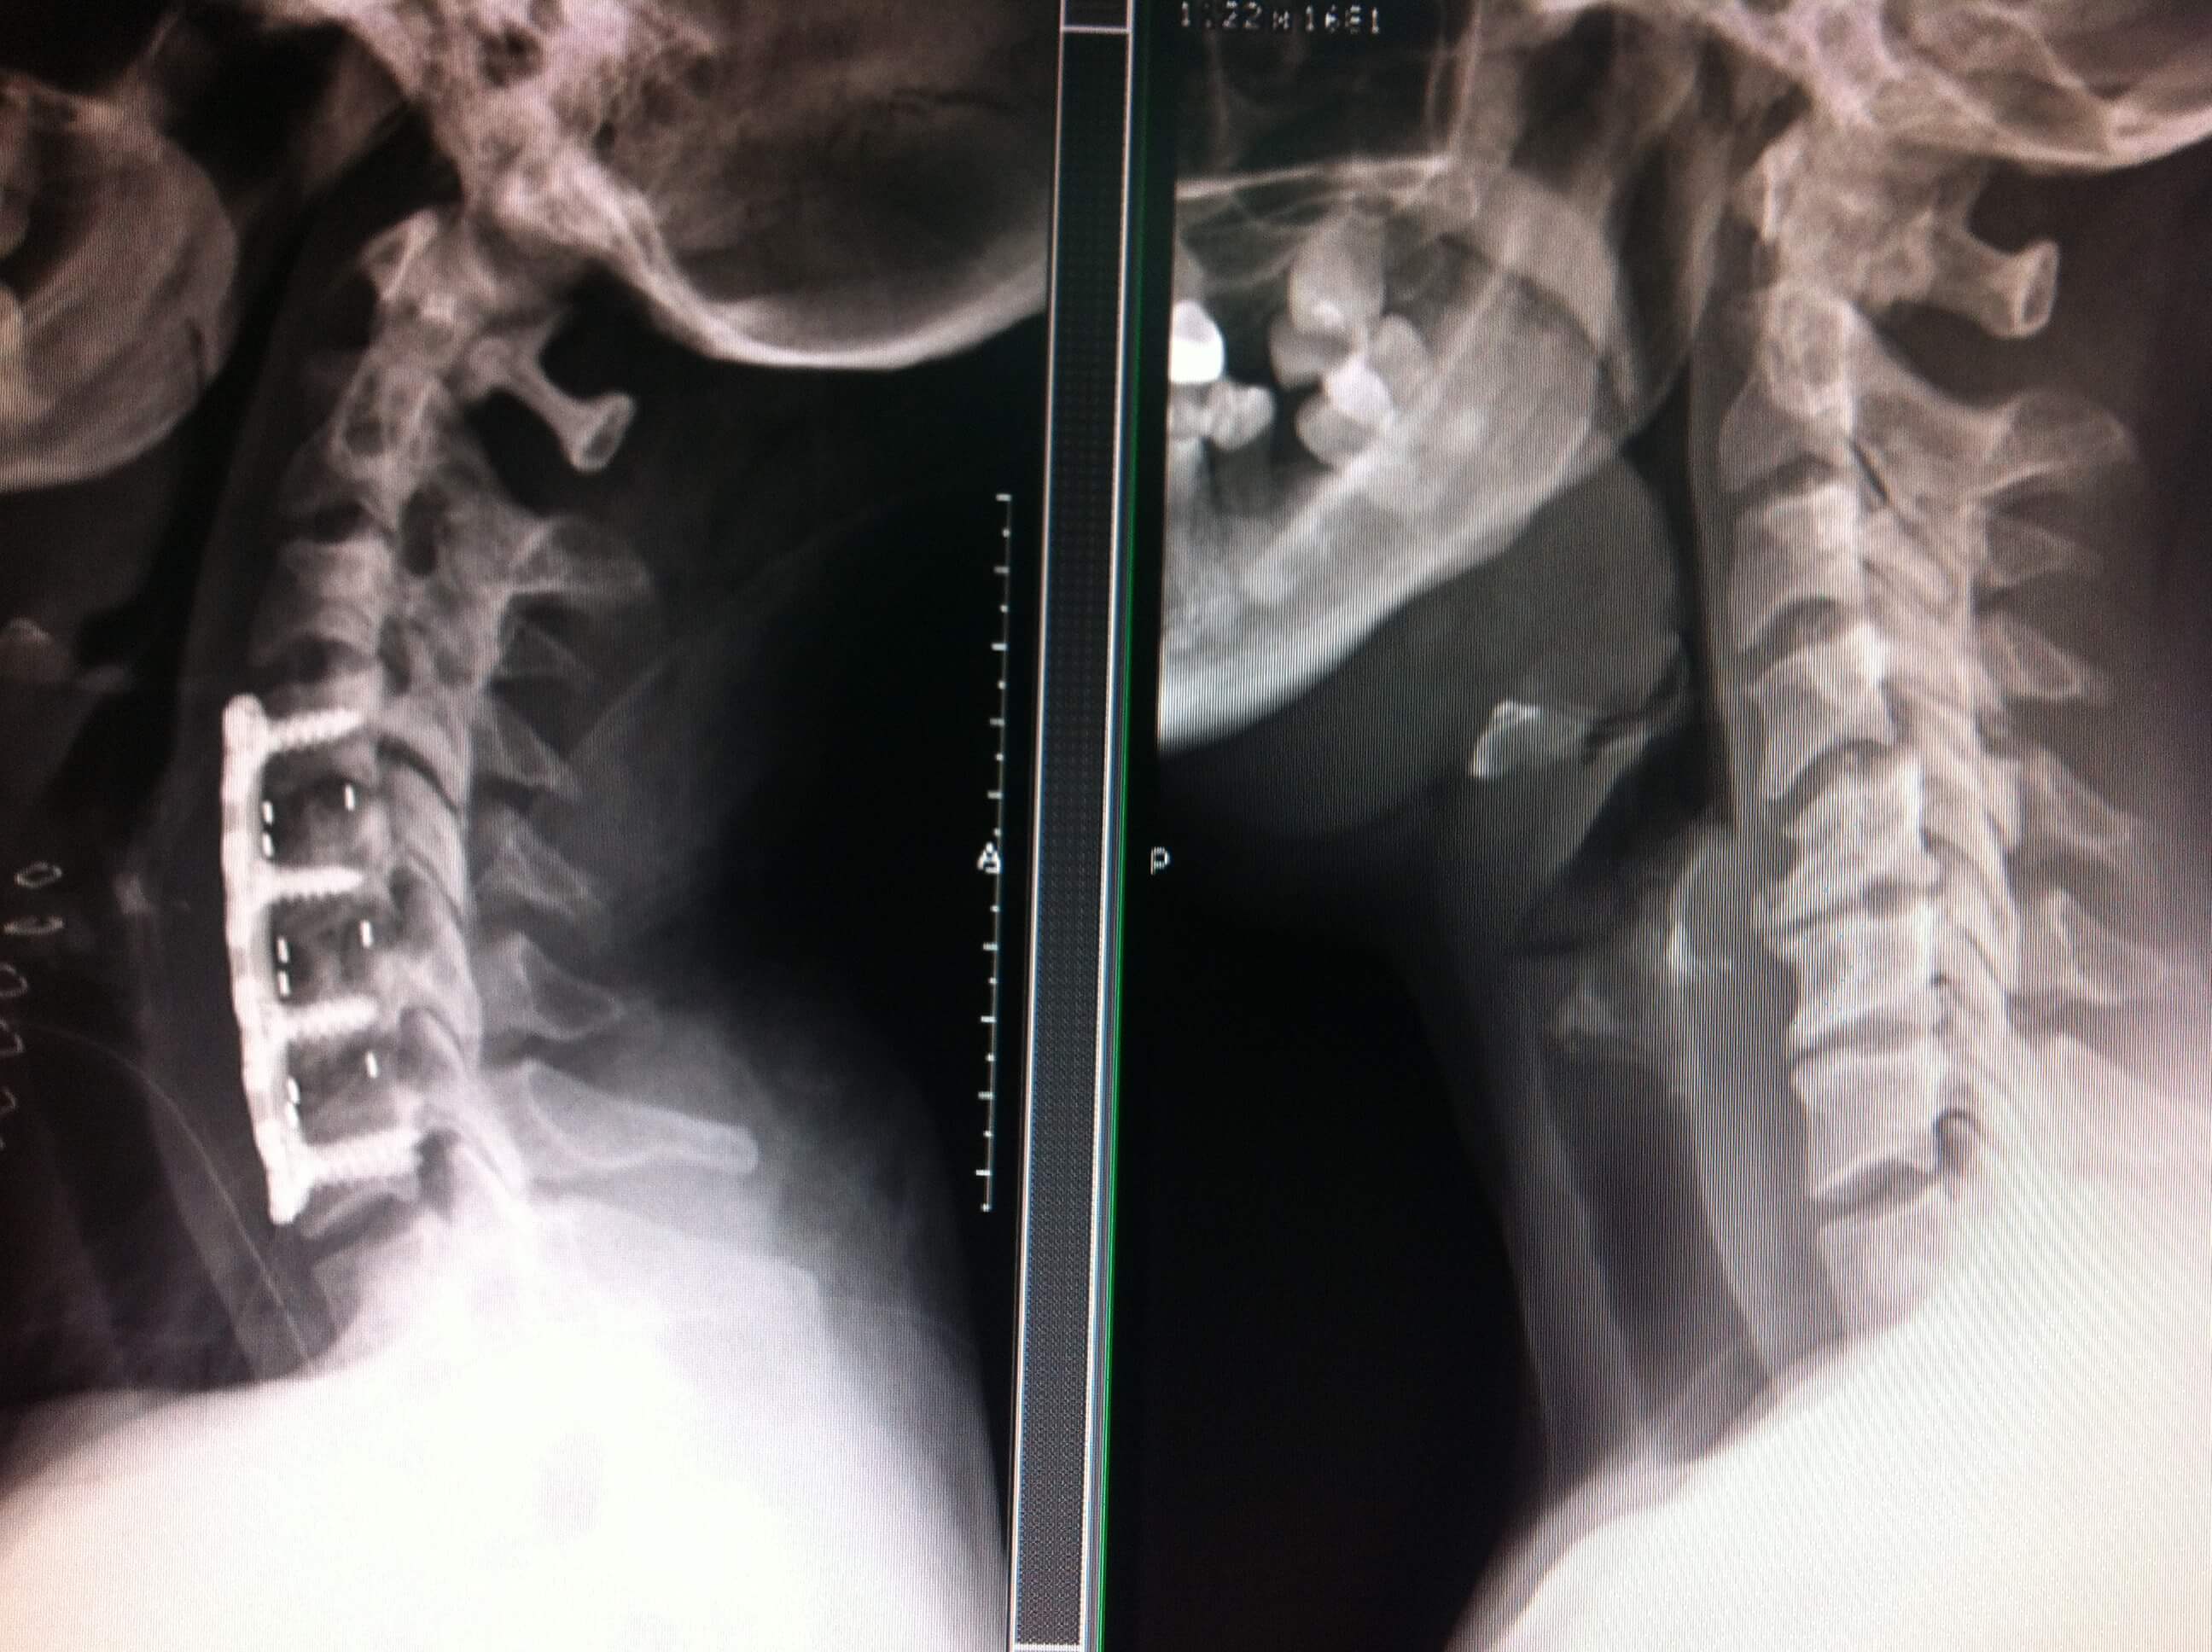

Grados De Discopatía Degenerativa Cervical, , , , , , , 0, Discopatia Degenerativa da Coluna Cervical - YouTube, www.youtube.com, 1280 x 720, jpeg, WebDolor y síntomas de la enfermedad degenerativa de disco cervical Además de sufrir el leve dolor producido por la rigidez y la inflexibilidad del cuello, muchos pacientes con. WebDiscopatía degenerativa. La discopatía degenerativa es una enfermedad que se presenta cuando uno o más discos en la columna vertebral pierden fuerza. Se trata de una., 20, grados-de-discopatia-degenerativa-cervical, Novedades y Muebles WebDolor y síntomas de la enfermedad degenerativa de disco cervical Además de sufrir el leve dolor producido por la rigidez y la inflexibilidad del cuello, muchos pacientes con. WebDiscopatía degenerativa. La discopatía degenerativa es una enfermedad que se presenta cuando uno o más discos en la columna vertebral pierden fuerza. Se trata de una.

WebLo primero que se debe saber es que la Discopatía Cervical es una lesión que aparece generalmente con los años, producto del desgaste y que en la mayoría de los casos. WebEsta es una forma de Tratamiento Biológico de las Discopatía Degenerativa en grado I, II y III de Pfirmann para tratar de regenerar el disco y para evitar la progresión de la. WebLa discopatía degenerativa no es, en realidad, una enfermedad. Pero eso no hace que el dolor que causa sea menos real. Independientemente de si es el resultado del. WebLa discopatía degenerativa cervical se diagnostica cuando un disco dañado de la columna se vuelve sintomático. Aprende más: https://www.spine-health.com/espa...

WebLa Discopatía Degenerativa y el dolor lumbar. El disco intervertebral es el «alma y corazón» de la columna. Son 7 a nivel cervical, 12 a nivel dorsal y 5 a nivel. WebDefinimos la Espondiloartrosis cervical o Espondilosis como cambios de carácter degenerativo que se relacionan con la edad. Hasta el 85 % de los mayores de 60 años. WebEl diagnóstico de la discopatía degenerativa suele ser realizado mediante una evaluación física, con especial detenimiento y detalle en la espalda,.